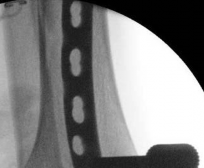

Fibular Fixation Strategy

The role of fibular fixation in distal tibia fractures remains a topic of academic debate, but in the context of intramedullary nailing, it is often a highly valuable adjunct. Plating the fibula restores the length of the lateral column and corrects rotational malalignment, effectively converting a highly unstable distal tibia fracture into a more manageable, length-stable pattern.

Image

Fibular fixation is typically performed prior to tibial nailing. An open reduction and internal fixation utilizing a one-third tubular plate or anatomic distal fibula plate is standard. By stabilizing the fibula, the tendency for the distal tibia to drift into valgus during nail insertion is significantly mitigated.